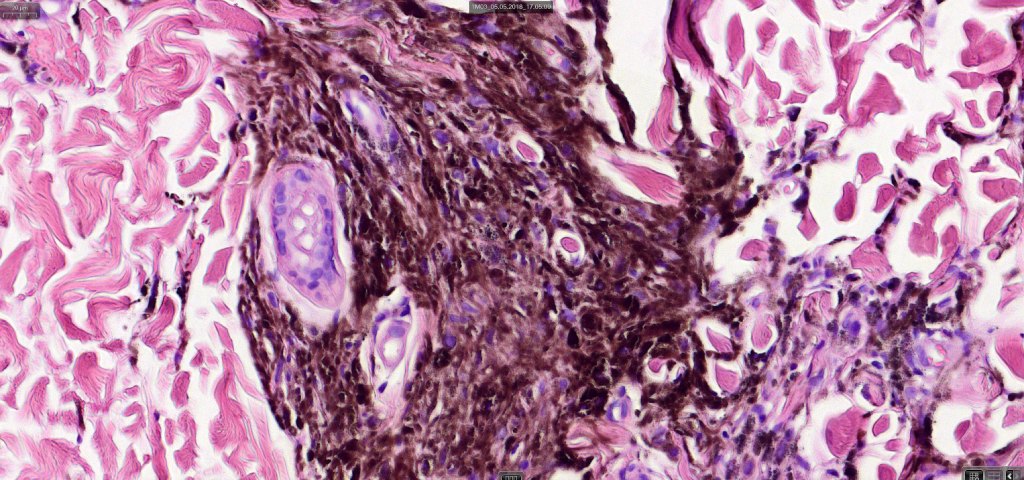

•Most characteristic is the dumbbell silhouette although a plague morphology may also be encountered

•Admixture of spindle cells, pigmented bipolar or dendritic cells & melanophages

•An alveolar pattern is characteristic particularly with clear cell nodules

•Stromal fibrosis, myxoid change, vascular hyalinization with cyst formation are often seen

•Some tumors are composed spindle cells in a fascicular or neuronevoid pattern

•Perineural involvement may be seen